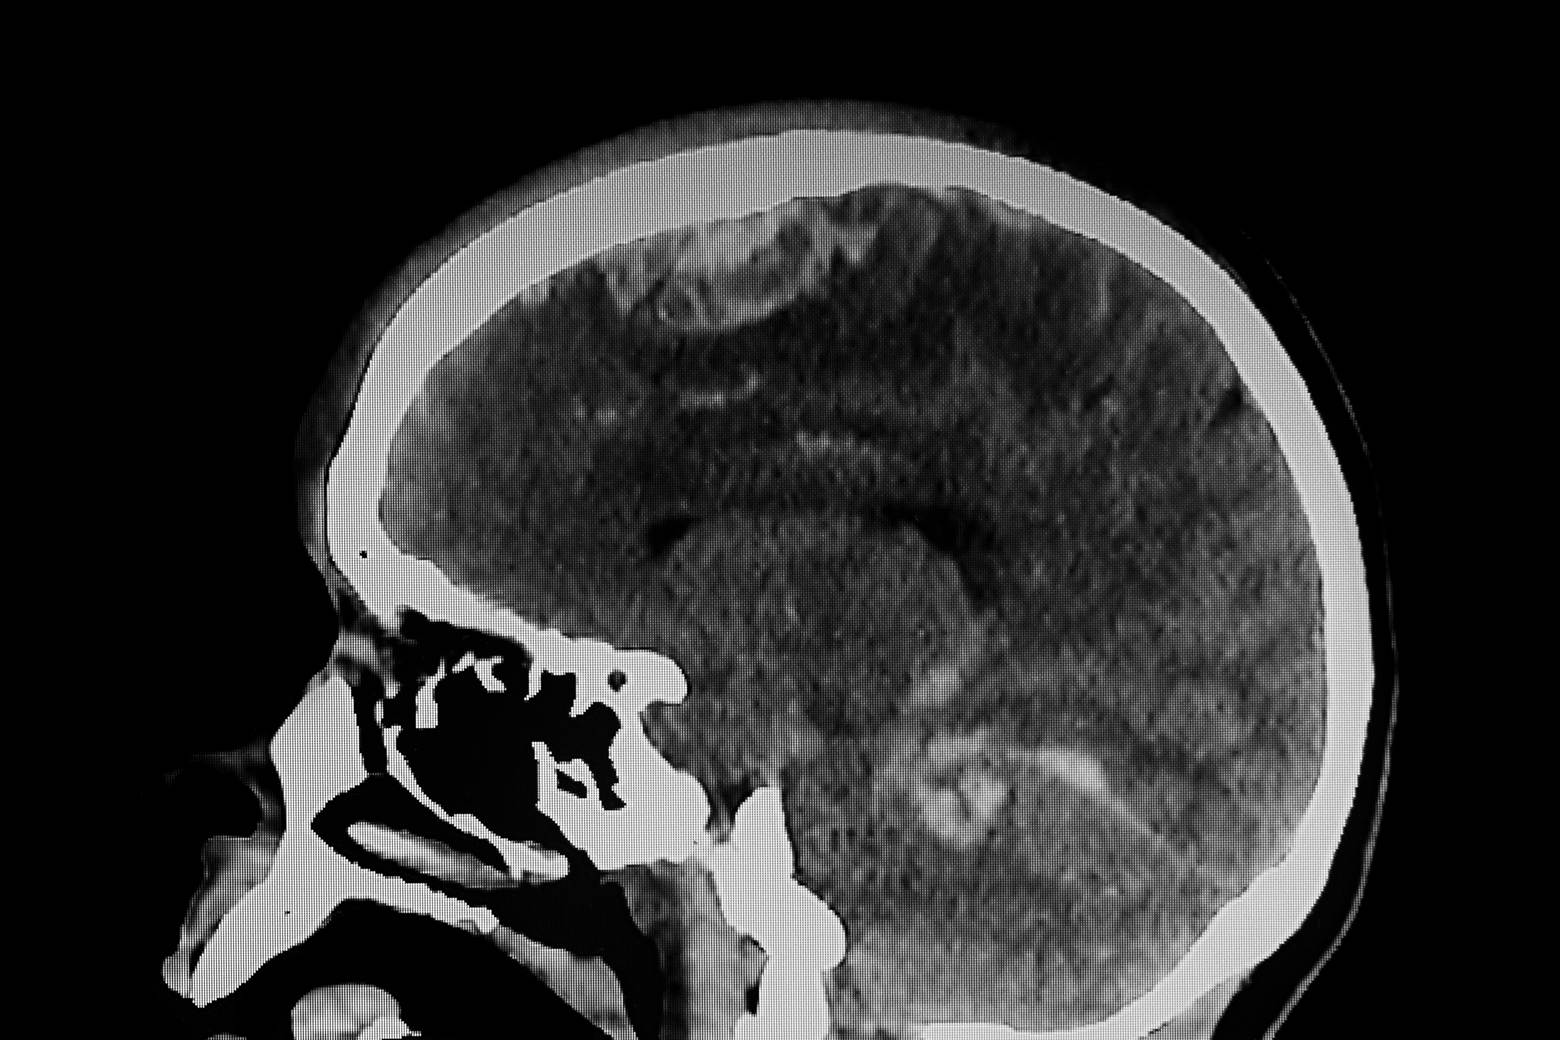

- Difficulty proving “invisible” injuries. It’s not always easy for a third-party observer to see how severely a concussion can disrupts someone’s life. Many symptoms are self-reported. Even visible signs of brain damage may not show up on an MRI, CT scan, or any other common imaging test, they just aren’t always sensitive to detect microscopic (but still severe) damage to brain structures. If you can’t prove your post-concussive syndrome with robust medical evidence, the insurance company may try to argue that you’re exaggerating your symptoms.